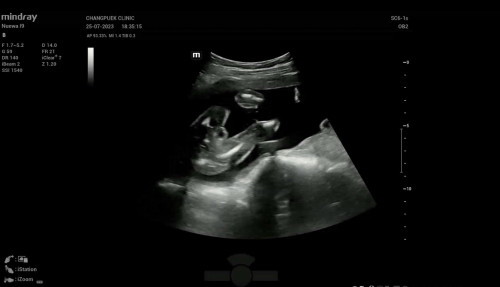

แม่ๆรู้เพศลูกกันยังค่ะ บ้านนี้มาเป็นกลีบเลย ไม่ต้องลุ้น 🤣👧🏻 20week6day#ท้องแรกคะ

บ้านนี้ได้ลูกสาวงับ🥰อ้าขาโชว์ไปเลย